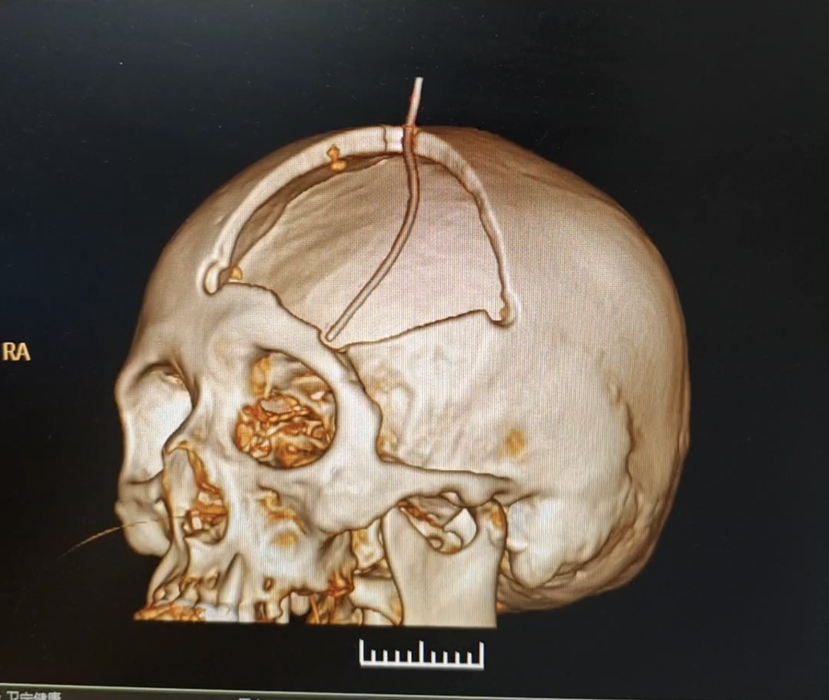

除了PEEK 钛网 本次用了超高分子量聚乙烯 颅骨修补